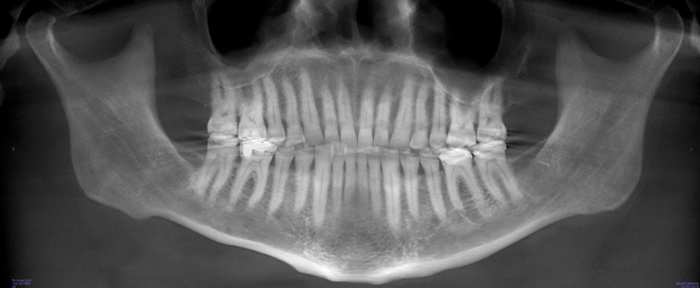

A comprehensive dental exam was performed that included a blood pressure test, an oral cancer screening, intraoral photographs, full mouth radiographs, a periodontal chart, a saliva test, and a CBCT scan. The exam confirmed the presence of active dental decay, periodontitis (ie, stage III, grade B), and areas of calcifications in his carotid artery (Figure 1 through Figure 3).

(3.) CBCT image of the patient’s airway.

Figure 3